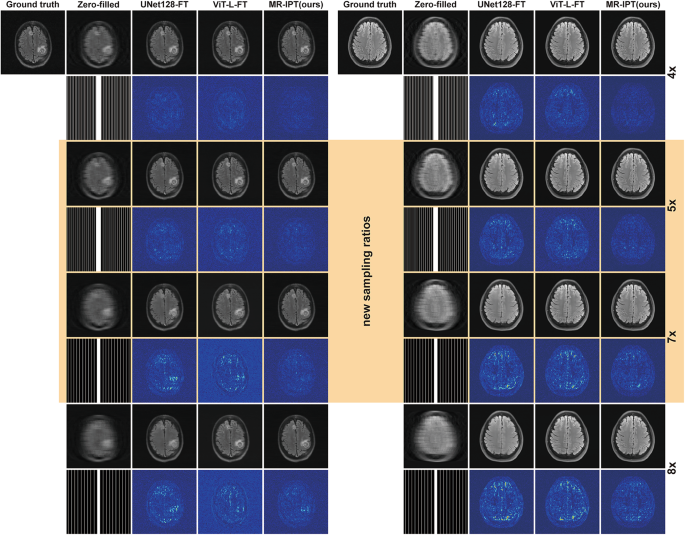

Figure 4 provides qualitative comparisons of reconstructed images. Interestingly, while ViT-L-FT and UNet128-FT exhibit differences in error map characteristics, UNet128-FT, despite having a higher maximum absolute error, produces cleaner backgrounds, particularly at higher acceleration ratios where overall image intensity is lower. MR-IPT consistently yields the cleanest error maps across all tested setups, including unseen sampling ratios, demonstrating its strong adaptability and generalization to novel acceleration factors.

Restoration comparison across multiple sampling ratios, including unseen configurations. This figure showcases the performance of different models in reconstructing MRI images at various acceleration ratios. Results highlighted in the yellow block represent new sampling ratios (e.g., 5× and 7×) that were not encountered during pre-training, demonstrating each model’s generalization ability. The results highlight MR-IPT’s strong adaptability to previously unseen acceleration factors, effectively preserving fine anatomical structures while minimizing artifacts, compared to other baseline methods.